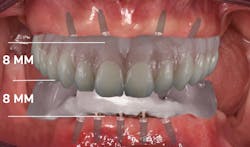

Figure 2: Bite block with anterior teeth

To do this, use a bite block to begin collecting measurements of what prosthetic thickness may be. Measure occlusal thickness and buccal and lingual width relative to proposed implant locations. You may also want to consider asking the lab to put two centrals on the wax-up so you can begin to establish the occlusal plane (figures 2 and 3).

Figure 3: Height and width